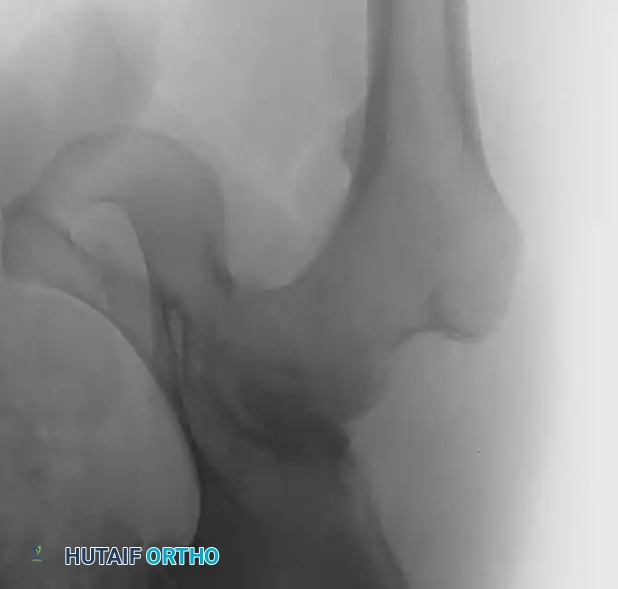

Associated Surgical & Radiographic Imaging

Hutaifortho's Orthopaedic Diagram